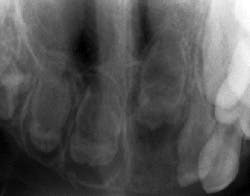

His treatment has consisted of some extractions with the placement of a partial denture to aid in tooth replacement and bone development. During your extraoral exam and review of his prior radiographs, you notice radiolucent areas in the posterior region that contain some slightly calcified structure, all having a very abnormal appearance. The term “ghost-like teeth” comes to mind as you view the early radiographs of Paul and you begin to remember what you learned about regional odontodysplasia in college.

Because of the limited areas affected, diagnosis is usually made with regard to RO by clinical and radiographic analysis. Radiographically, the teeth are seen as poorly developed with very little dentin or enamel showing calcification, thereby presenting with a less radiopaque appearance than a normally developed tooth. Because of this poor development and the lack of calcification, they have been termed “ghost teeth” with only a shadow of a tooth present (see Figure 2).